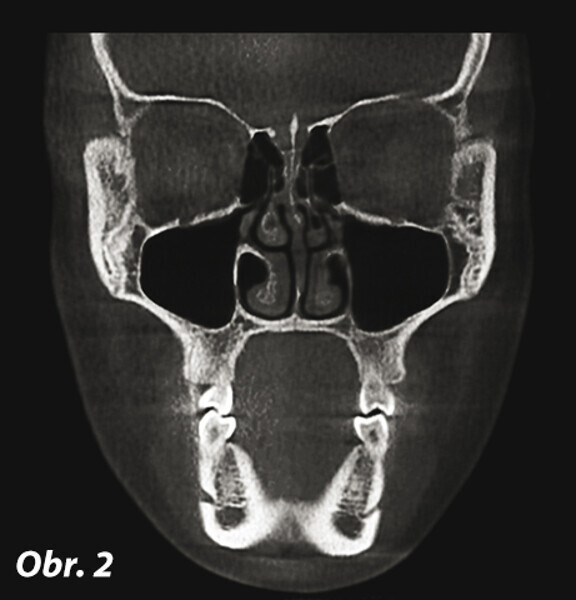

Význam 3D zobrazovacích systémů v současné ortodoncii